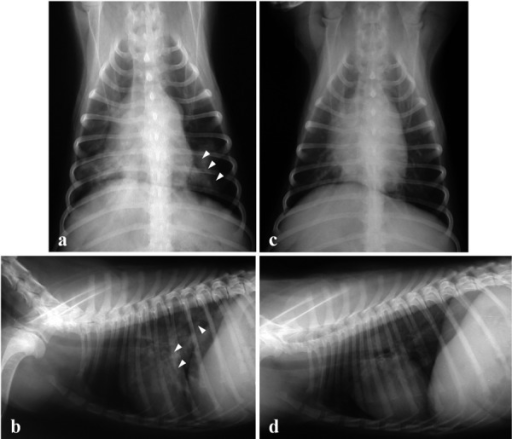

Aspiration Pneumonia In Dogs Central Toronto Veterinary Referral Clinic from ctvrc.ca A definitive diagnosis of lung cancer requires a sample of tissue (biopsy). Pneumonia is a lung infection that leads to breathing difficulties and fluid in the lungs. But in some rare cases, it may be a lung cancer (primary or secondary). My dog had pneumonia come on quickly this last august, we took her to the local er at 3am when we noticed her breathing labored and strange behavior. X rays are very helpful in the diagnosis of lung cancer in dogs. Typical signs of bacterial pneumonia include fever, difficulty breathing, lethargy and coughing. A retrospective study of 1011 hospitalized patients with pneumonia was undertaken to assess the value of routine convalescent chest radiography for detection of underlying lung cancer. The bronchioles end in the small sacs called.

A definitive diagnosis of lung cancer requires a sample of tissue (biopsy). X rays are very helpful in the diagnosis of lung cancer in dogs. Primary lung cancer are frequently located in the caudal (towards the hind end of the pet) lung lobes, however can be located in any lung lobe and are usually a single mass in the lungs, unless the tumor has spread. If your dog has a chronic cough, you'll need to rule these out. The first of these possibilities could be investigated by bronchoscopy. A definitive diagnosis of lung cancer requires a sample of tissue (biopsy). The second kind of lung cancer in dogs is called metastatic lung cancer, which means the cancer originated somewhere else in the body, but has spread to the lung. Bacterial pneumonia is an inflammation of the lung usually caused by bacterial or viral infection but can be caused by inhalation of an irritant. The respiratory system consists of the large and small airways and the lungs. Lung cancer is actually the number one killer when it comes to cancers. But in some rare cases, it may be a lung cancer (primary or secondary). In both cases, you may have. Typical signs of bacterial pneumonia include fever, difficulty breathing, lethargy and coughing.

Primary lung cancer are frequently located in the caudal (towards the hind end of the pet) lung lobes, however can be located in any lung lobe and are usually a single mass in the lungs, unless the tumor has spread. My dog had pneumonia come on quickly this last august, we took her to the local er at 3am when we noticed her breathing labored and strange behavior. A white spot amidst the normal black lungs can therefore be a cancer, infection. Signs of the primary tumors in dogs. I haven't touched cigarettes a day in my life. Lung cancer often misdiagnosed as pneumonia urges requests for second medical opinions. Lung cancer is actually the number one killer when it comes to cancers. A definitive diagnosis of lung cancer requires a sample of tissue (biopsy). His appetite is basically normal though his blood work shows that he is anemic. 3 doctors agree send thanks to the doctor Other common respiratory diseases that might make you worried about cancer are …. Malignant tumors trigger inflammation in surrounding normal lung tissue, and they may obstruct. Pneumonia and lung cancer both affect the lungs but one is easily treatable and the other is potentially life threatening.